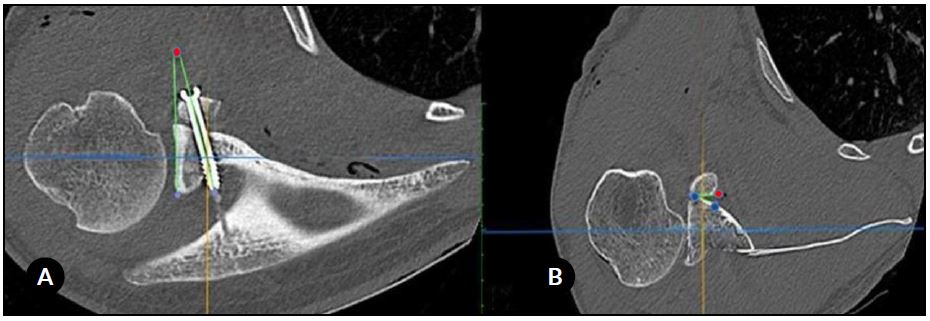

Se mostraron simultáneamente en la misma pantalla las imágenes en 2 planos (sagital y axial). Luego se realizaron las siguientes 4 medidas para cada paciente: (A) la posición del injerto coracoideo en el plano sagital, (B) la posición del injerto en el plano axial, (C) la dirección de los tornillos (ángulo), y (D) el ángulo de contacto (Figs. 1 y 2).

En el plano axial, el injerto coracoideo se consideró “al ras” cuando el borde lateral del injerto estaba entre 1 mm lateral y 4 mm medial a la línea articular; “medial” cuando estaba >4 mm medial a la línea articular; y “prominente” cuando era >1 mm lateral a la línea articular. El ángulo α se definió como el ángulo entre el eje del tornillo y el hueso subcondral glenoideo. Finalmente, el ángulo de contacto fue el ángulo formado entre la superficie posterior del injerto coracoideo (medido entre los 2 tornillos) y el cuello anterior de la glena. Se consideró contacto completo si el ángulo era ≤4 e incompleto cuando era >4. Si el espacio entre el injerto y la glenoides era >1 mm, asumimos que no existía contacto.16

Figura 2. A) Cálculo de la dirección del tornillo (ángulo). El punto rojo indica el ángulo formado por el eje del tornillo y el hueso subcondral glenoideo (líneas verdes). B) Evaluación del contacto del injerto coracoideo con la superficie glenoidea anterior. El ángulo de contacto se define desde la superficie posterior del injerto coracoideo (línea verde entre los puntos rojo y azul) y el cuello anterior de la cavidad glenoidea (línea verde entre los 2 puntos azules).